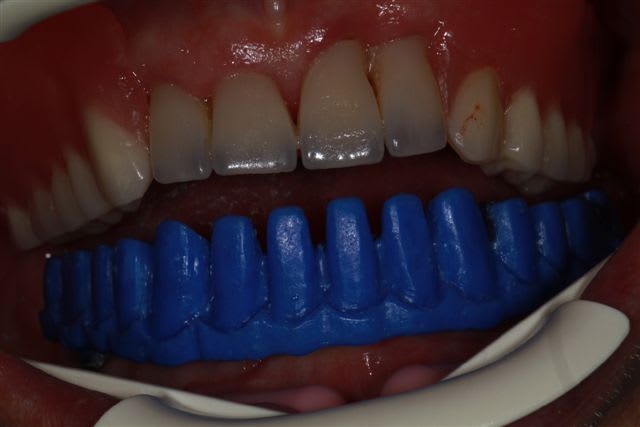

et dans le même esprit, il n'y a pas que la cadcam, ce matin essayage de la maquette (résine calcinable+cire)pour controler l'ajustage et surtout valider la préforme pour l'occlusion,et la position des incisives.

Moralité nous allons repositionner la fausse gencive et les incisives...(ce sera une barre avec emax press dessus)

La prise d'empreinte s'est faite en occlusion en se servant de fac simile translucides en résine préparés à partir de la prothèse totale haut et bas fabriquée dans un premier temps.